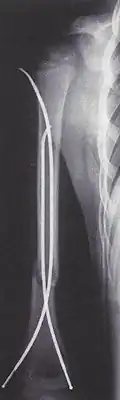

Weitere Neuerungen bei der Marknagelung waren etwa 1961 die Markraumschienung mit Bündelnagelung nach Karl H. Julius Hackethal, wodurch Übungsstabilität erzielt wurde, und der bis 1966 von H-J. Kaessmann und H. G. Weber als Modifikation des Küntscher-Nagels entwickelte Kompressionsnagel,[5] bei dem durch eine Spannvorrichtung die Knochenfragmente durch axialen Druck fixiert und somit ein Ausbohren der Markhöhle vermieden wurde.[6]

Der heutige Stand der Technik sind Marknägel aus weitgehend inertem Titan. Diese Implantate bieten die Möglichkeit einer statischen oder dynamischen Verriegelung sowie einer Kompression auf den Frakturspalt. Versorgt werden geschlossene und einfach offene Frakturen der großen Röhrenknochen (Oberschenkel (Femur), Schienbein (Tibia), Oberarmknochen (Humerus) ). Andere Versorgungen stellen Außenseiteranwendungen in Spezialfällen dar. Für gelenknahe Frakturen an oben genannten Knochen gibt es eine Reihe von Spezialimplantaten mit besonderen Eigenschaften wie z. B. den Gammanagel, proximalen Humerusnagel oder distalen Femurnagel. Die Implantate sind auf den Zielknochen anatomisch vorgeformt und in verschiedenen Dicken und Längen erhältlich.